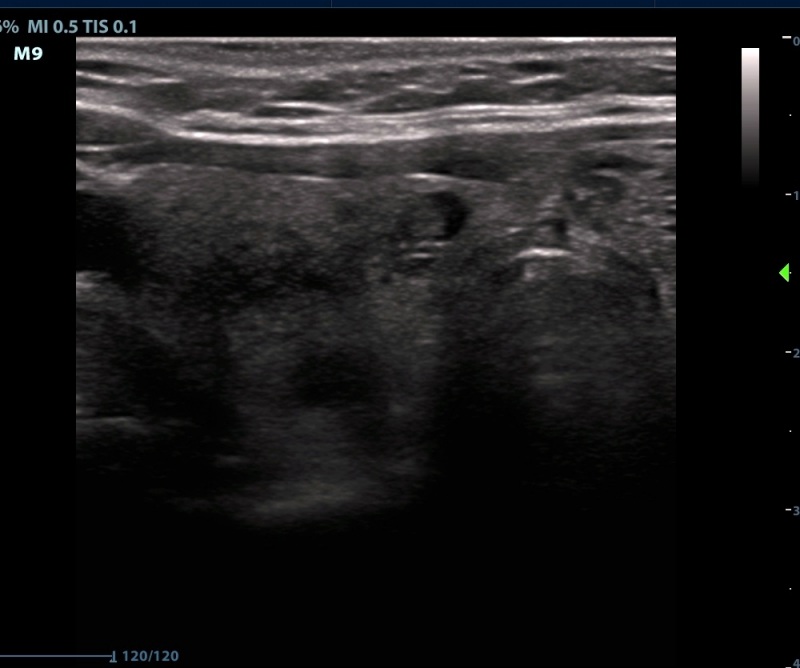

Ultrasonography. The thyroid was echonormal. There were numerous discrete lesions in the right lobe. There was a dominantly solid, echonormal nodule in the isthmus and an almost completely cyst in the left lobe.